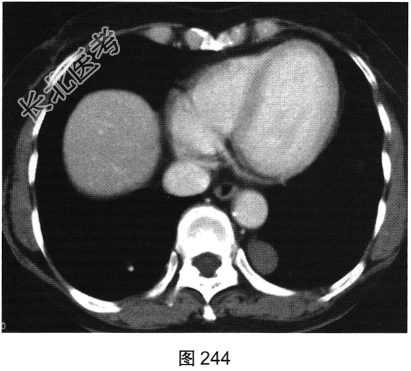

- 多项选择题3.[提示]患者增强CT如图243、图244所示。下述哪些征象的描述是正确的( )

A、可出现气液平面

B、增强扫描无明显强化

C、囊性病变也可表现为平扫高密度

D、MRI对本例病变的鉴别诊断没有帮助

E、如病灶内可见支气管穿行进入,则可定位在肺内

F、神经源性肿瘤常可见椎间孔扩大

- 多项选择题4.根据上述临床资料与CT表现特点,该患者最可能的诊断是( )

A、淋巴管瘤

B、神经源性肿瘤

C、肺脓肿

D、孤立性纤维瘤

E、支气管闭锁

F、支气管囊肿

G、脊膜膨出

H、肺隔离症